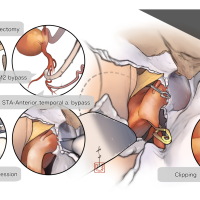

FEN2022シリーズ